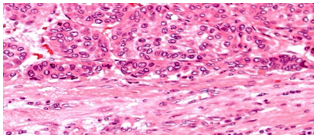

Biopsy

Gross HCC - Liver Cirrhosis (HBV – HCV)

cirrhotic, tumour round homogenous on right lobe